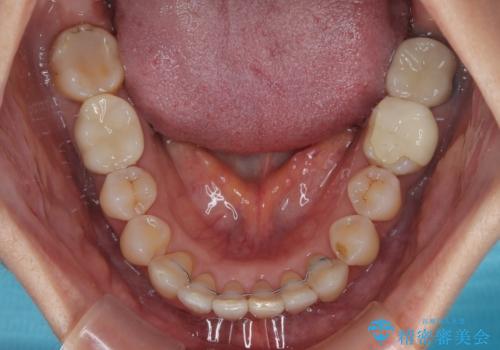

- 上下前歯のデコボコと、奥歯の銀歯を気にして来院された患者様です。

仕事柄あまり目立つ装置は付けることは避けたいとのことで、インビザラインによるマウスピース矯正を行うこととしました。

概ね歯列が整ったところで銀歯の全てをセラミッククラウンなどに置き換え、その後インビザラインを1セット使用して仕上げていくこととしました。